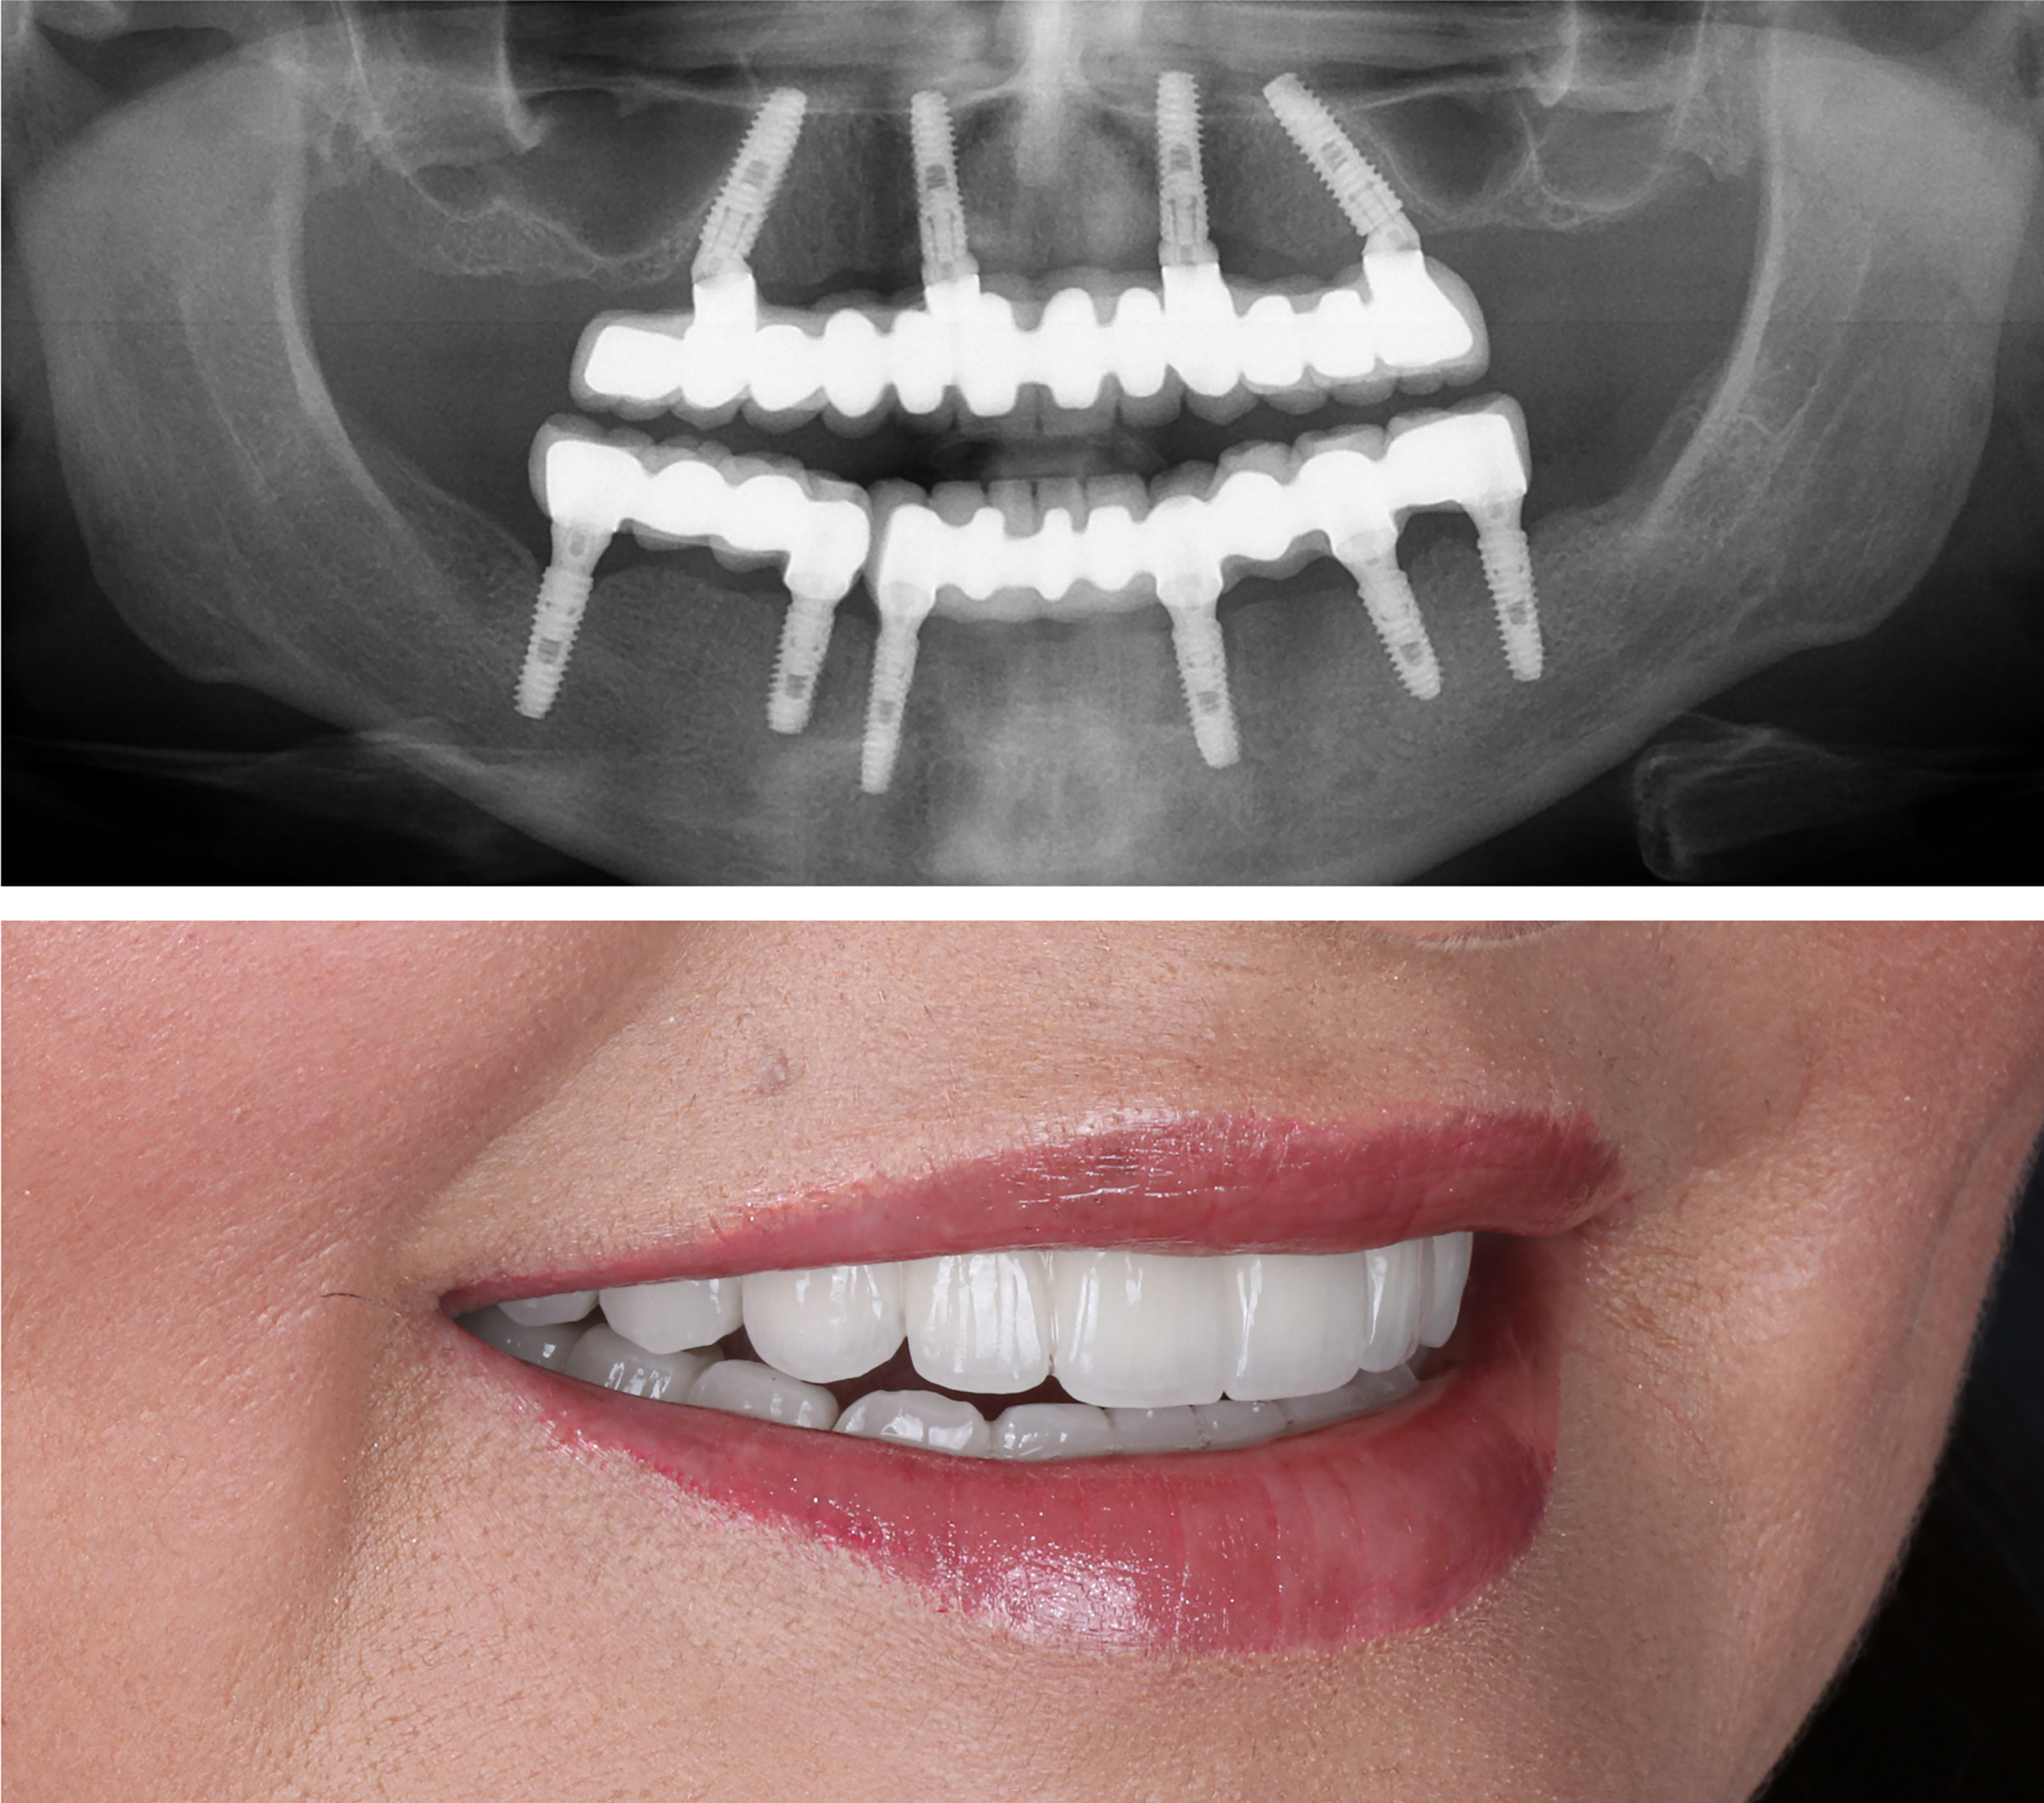

Example transformations achievable with dental implants

So, how do they work?

Every single dental implant consists of three parts - the implant, the abutment, & the crown. The implant is made of medical grade titanium. This part is surgically placed into the patient’s jaw bone and left to heal for 4-6 months afterwards.

This implant piece acts as the foundation for the rest of the tooth. Once the bone around the site has healed, the abutment and crown are placed on top of the implant. The end result is a beautiful, natural-looking new tooth!

Few people will ever be able to tell the difference between your implants and your real teeth.